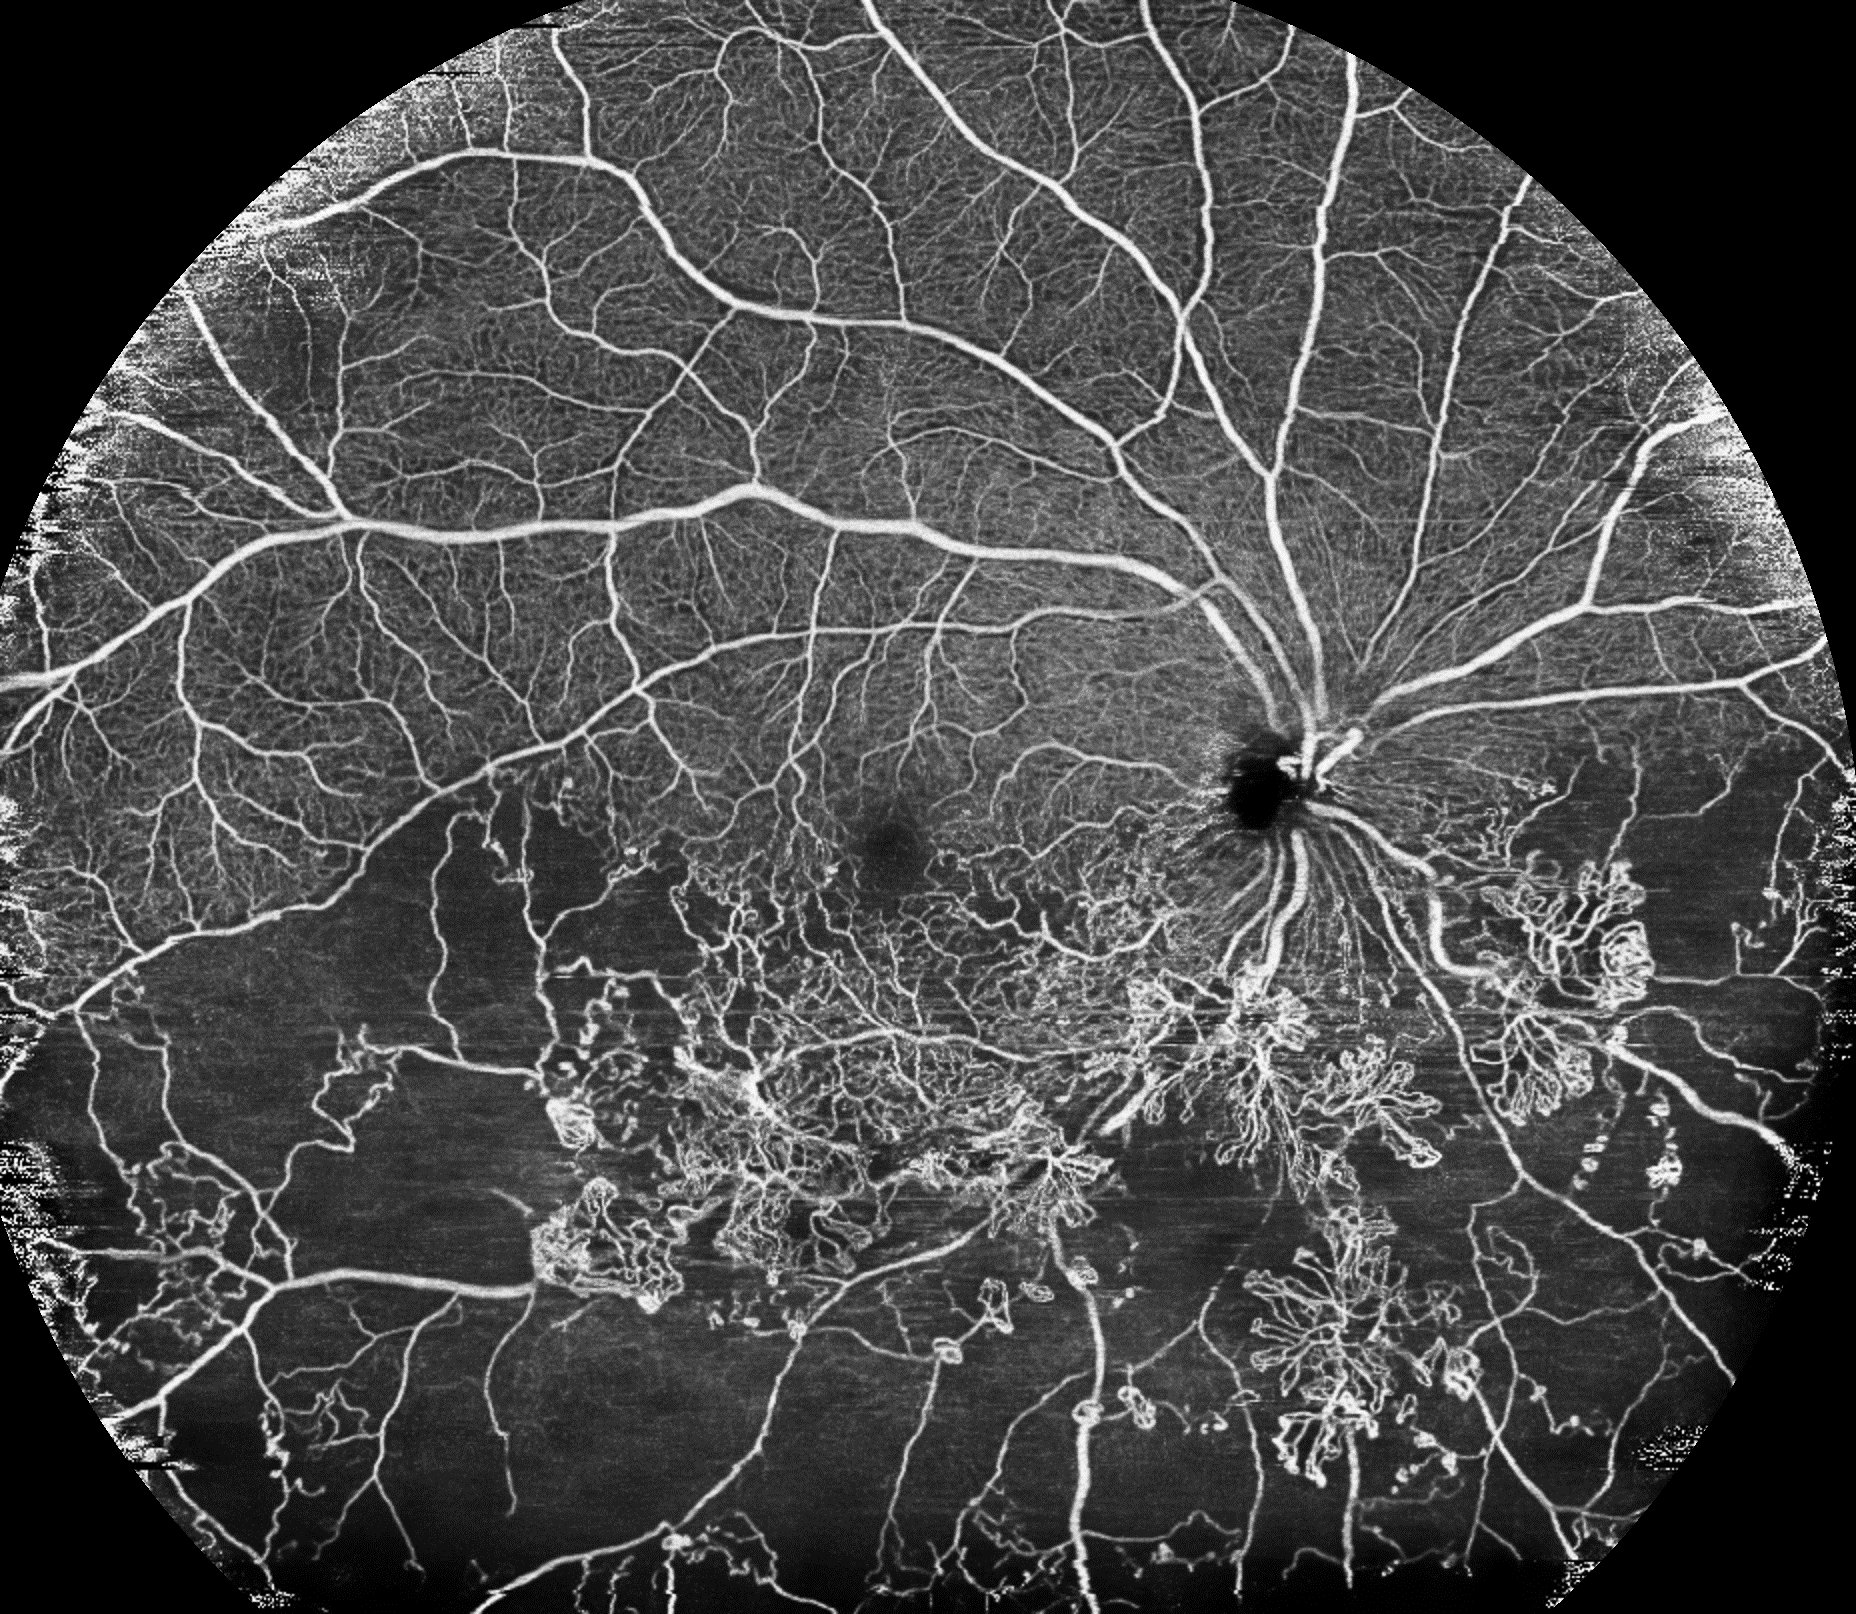

Унікальна технологія обробки зображень Canon забезпечує створення ширококутних зображень високої чіткості ОКТА

Ширококутне OКТА - зображення з кутом 80 градусів* дозволяє ідентифікувати судинні аномалії (такі як зони неперфузії та неоваскуляризації) через захворювання, включаючи діабетичну ретинопатію та артеріовенозну оклюзію, за один сеанс, що значно зменшує навантаження на об’єкта дослідження порівняно зі звичайним панорамним зображенням. Крім того, «інтелектуальне усунення шумів» також використовується в ширококутних OКTA. Це дозволяє отримувати зображення високої чіткості. Ці зображення покривають широку ділянку і дозволяють перевірити стан капілярів.

*Горизонталь 78°, вертикаль 68° (23 × 20 мм)

Ширококутне зображення високої чіткості OКТA, яке також дозволяє перевірити стан капілярів (рис.5)